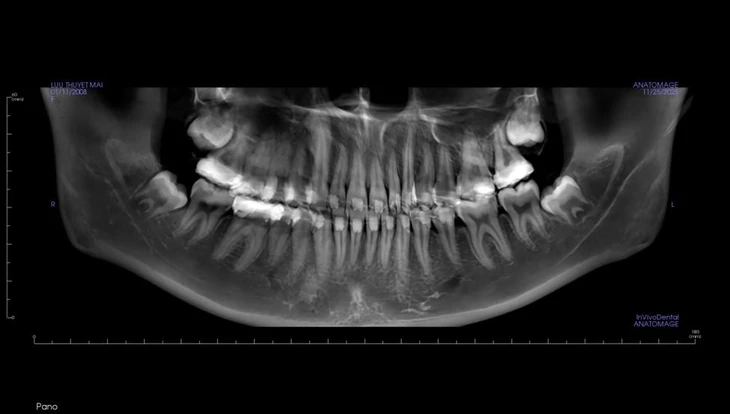

Pada X-ray, pesakit mempunyai 4 gigi geraham bungsu impak yang perlu dicabut - Foto: BSCC